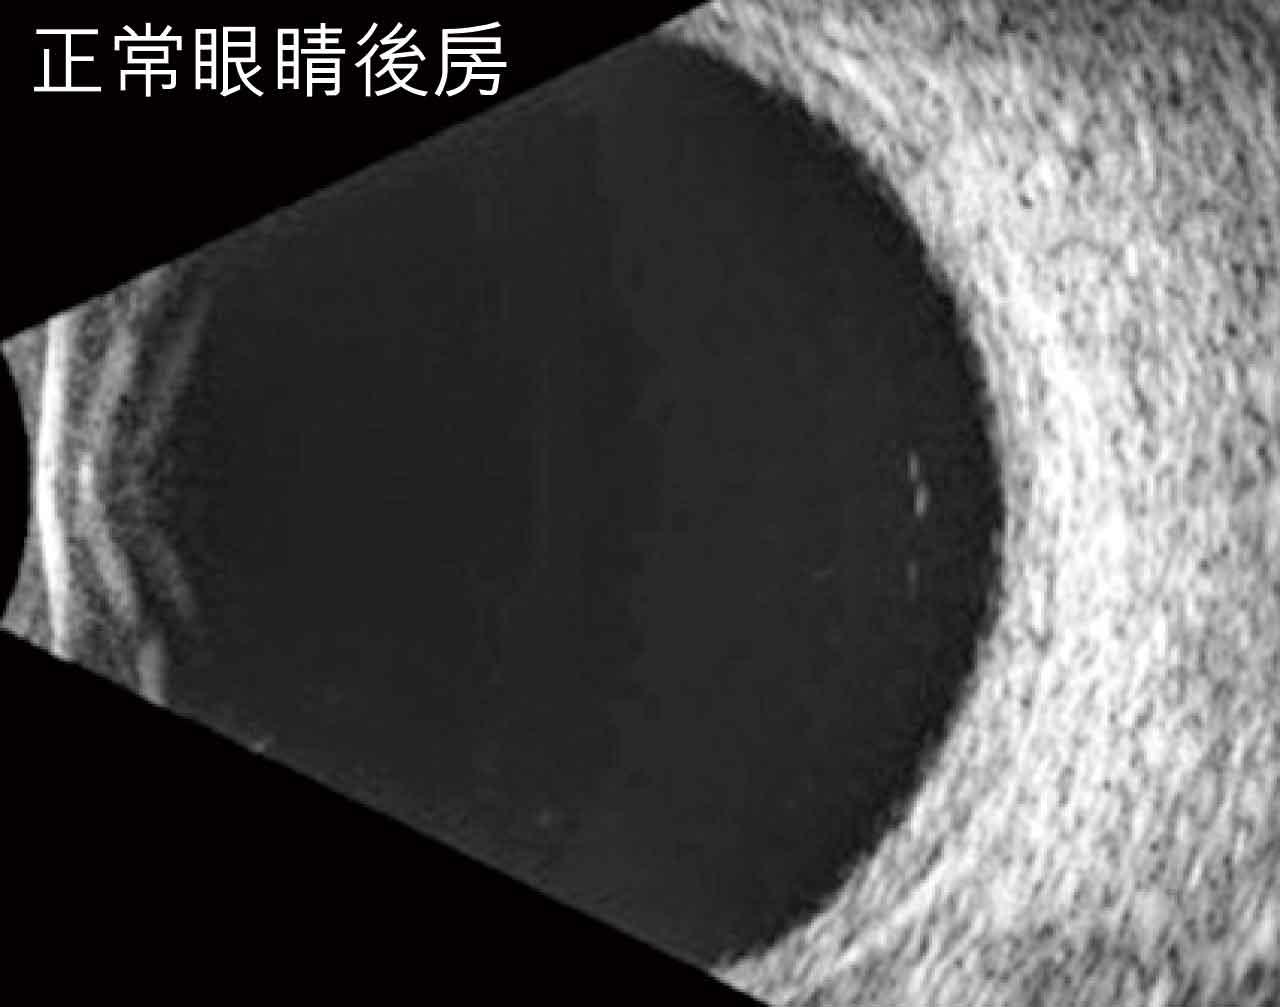

正常眼睛後房

我們之所以能夠看見影像,是由於物件反射光波進入眼球。一般情況底下,當眼睛角膜和晶體清澈透明,我們能夠透過肉眼檢查眼底的視網膜和視神經。但在特殊情況下,例如角膜出現嚴重疤痕或水腫,或者晶體完全混濁毫不透光的話,那麼我們便要依賴超聲波檢查眼底的狀況。

超聲波的原理,就像潛水艇或者一些深海魚類,透過發出聲波,然後經前方物件反彈,再經過接收器去回收這些訊號,去分析訊號發射器和前方物件之間的距離。基於不同物質的密度,反射的聲波訊號有強有弱,形成我們在超聲波上見到的黑白灰。

甚麼時候醫生會使用超聲波去替病人檢查眼睛呢?除了熟透了的白內障,我們最常見的就是糖尿上眼患者可能會面對的玻璃體出血、各種不同類型的視網膜脫落,以及眼內發炎導致前房及玻璃體的混濁等。眼睛超聲波除了能夠分析眼球後房,亦有專門檢查前房的探頭。利用一個較高頻率,能夠窺探到肉眼不能看見的結構,例如虹膜背後的睫狀體,晶體旁邊的懸索帶,尤其適用於瞳孔過小,或眼球受過創傷的病人。這類型超聲波非常適合眼睛前節的手術前評估,和手術後的監察。總而言之,眼部超聲波是我們眼科診所裡一個不可或缺的重要檢查項目!